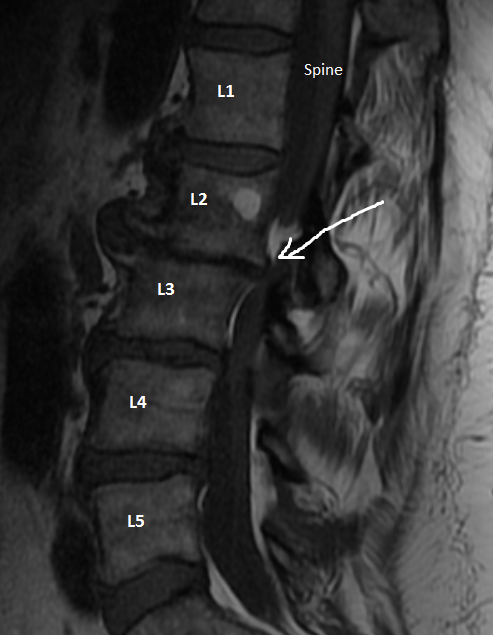

The force of this event, smashed the L2-L3 joint in my spine destroying the disk and breaking the vertebrae. The force traveled down my right leg, dislocated and broke my fibula (bone on the outside of the lower leg).

On August 22, 22 years later, I'm going in to have this section of my back repaired with a 3 level fusion.

- We waited until I was completely unable to get around (which is now). If you look at the arrow, the vertebrae has moved to cut off most of my spine. This means that I have lost a lot nerve interaction in my legs.